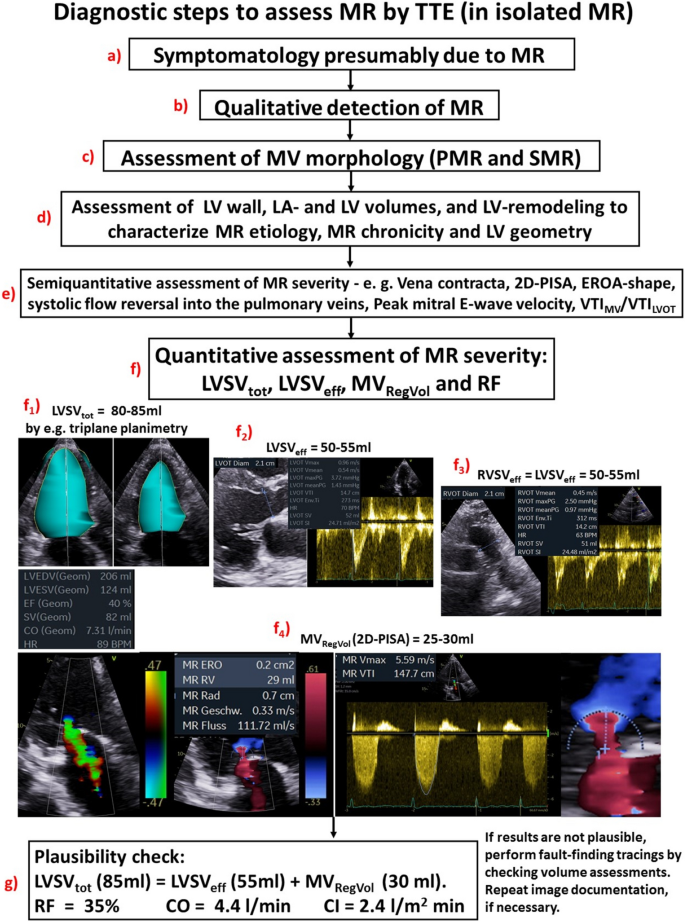

Graphic abstract

The echocardiographic examination should consider and interpret the clinical symptoms, and the individual patient`s factors in relation to the presumed valvular defect (Figs. 3, 4). After qualitative MR detection by Doppler techniques, the next diagnostic steps by echocardiography should be the assessment of mitral valve (MV) morphology, LV wall thickness, left atrial (LA), and LV volume as well as LV shape and remodelling, prior to grading MR severity (Figs. 3, 4). Thereafter, a semi-quantitative MR assessment is advised, which should be followed by a quantification of MR severity, if moderate or severe MR is being suspected, or if severity of MR remains unclear (Fig. 4). Every changes of MR severity documented by repetitive standardized echocardiography should be noted to enable reliable conclusions about the respective treatment effects. Figure 5 depicts a recommended timeline for performing echocardiographic examinations in patients with significant MR who are considered for interventional/surgical treatment of MR.

Scheme to illustrate the echocardiographic workflow to assess MR severity: After interpretation of symptomatology with respect to the causal relationship to the MR qualitative MR detection results in MR classification due to the MV morphology. Echocardiographic parameters of LA and LV size and LV wall thickness characterize loading conditions and enable to distinguish between pressure or volume overload and between compensated or decompensated conditions. The assessment of MR severity starts with the integrated approach and the analysis of semi-quantitative parameters. The final experts’ task of analysis of MR severity is the quantitative assessment of LVSVtot, LVSVeff, MVRegVol, and RF as a plausibility check. At every level of the assessment of MR severity expert consultation as well as the quantitative analysis of MR severity should be considered with respect to severe symptoms, signs of volume overload and heart failure as well as incongruent results by the grading of MR severity by the semi-quantitative approach. 2D two-dimensional, EROA effective regurgitant orifice area, LA left atrial, LV left ventricular, LVOT LV outflow tract, LVRI LV remodelling index, LVSVeff effective LV stroke volume, LVSVtot total LV stroke volume, MR mitral regurgitation, MV mitral valve, MVRegVol regurgitant MV volume, PISA proximal isovelocity surface area, PMR primary MR, RF regurgitant fraction, RWT relative wall thickness, SMR secondary MR, VTI velocity time integral